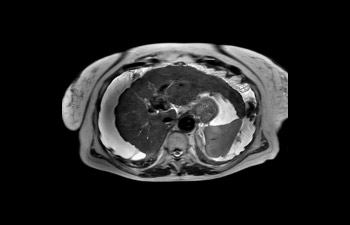

Liver with ascites